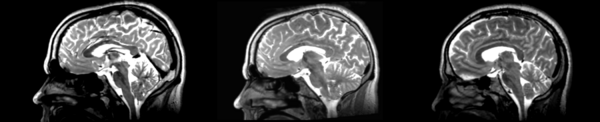

Different subject registration

In this, I'll be moving images like so:

- 01053-t2 -> 01031-t2 = Result. All the images shown have the moving image on the left, the resultant image in the middle, and the target image on the right.

Slicer modules

Rigid

01053>01031rigid.png = not bad... different brains of different sizes, but seem to be aligned in the ventricles so output seems okay. output slightly blurry. bad initial leveling displays.

Linear

01053>01031linear.png = not bad... different brains of different sizes, but seem to be aligned in the ventricles so output seems okay.output slightly blurry. bad initial leveling displays.

Affine

01053>01031_affine.png = looks good in terms of size. odd warping of frontal lobe and cerebellum area, but otherwise good coregistration.

B-spline

01053>01031_bspline.png = looks good in terms of size. odd warping of frontal/temporal lobe and cerebellum area, but otherwise good coregistration.

Diffeomorphic Demons

01053>01031_demons.png = 10 minutes. Window/leveling initially off. Otherwise, it looks really good. Not much distortion.